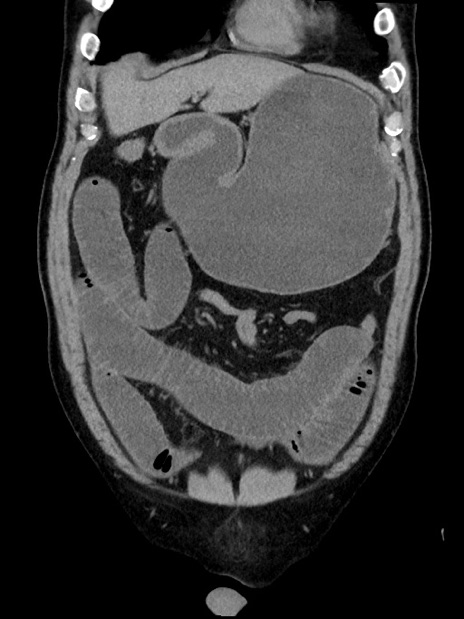

症例35(冠状断像)

【症例】70歳代 男性

【主訴】腹部膨満、嘔吐

【現病歴】昨日より腹部膨満感出現。本日増悪し、仙痛出現。嘔吐あり、受診。

【既往歴】糖尿病、胆摘後

【身体所見】BP 149/80mmHg、HR 74/min、BT 35.9℃、腹部:膨満、軟、圧痛なし。腸雑音減弱あり。上腹部正中切開瘢痕あり。

【データ】WBC 13500、CRP 1.72